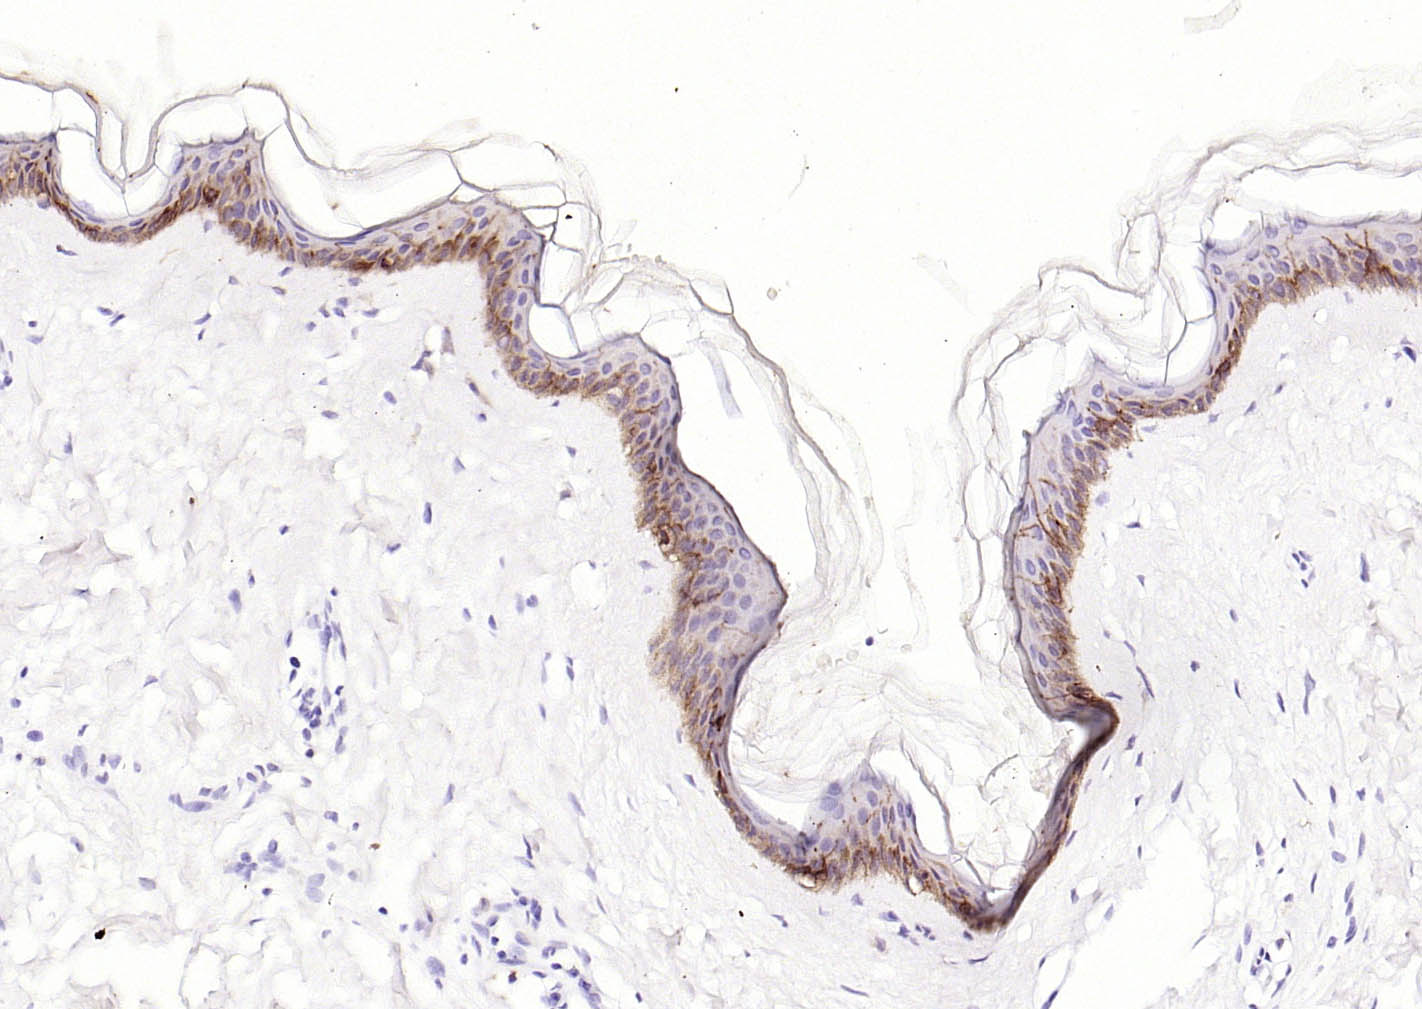

Paraformaldehyde-fixed, paraffin embedded (human Abdominal skin); Antigen retrieval by boiling in sodium citrate buffer (pH6.0) for 15min; Block endogenous peroxidase by 3% hydrogen peroxide for 20 minutes; Blocking buffer (normal goat serum) at 37°C for 30min; Incubation with (CD1A ) Monoclonal Antibody, Unconjugated (bsm-60907R) at 1:200 overnight at 4°C, followed by operating according to SP Kit(Rabbit) (sp-0023) instructionsand DAB staining.